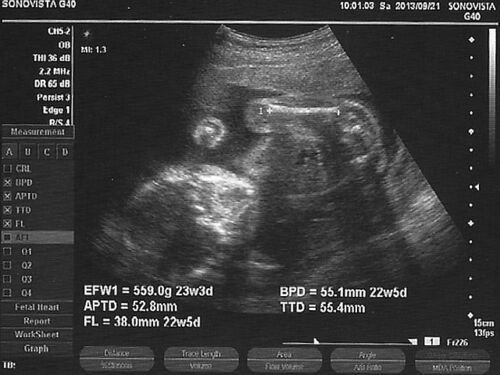

てらじNext(仮)開発経過(Week23)

引き続き開発は順調です。開発主任が「立ち座りがちょっとキツい」と言っているので、テーブルと椅子を注文しました。主任の体重は目立っては増えていませんが、腹囲はだいぶ目立ってきました。何故かワシの体重が増えてます。 だいぶ完成に近い形に見えてき…